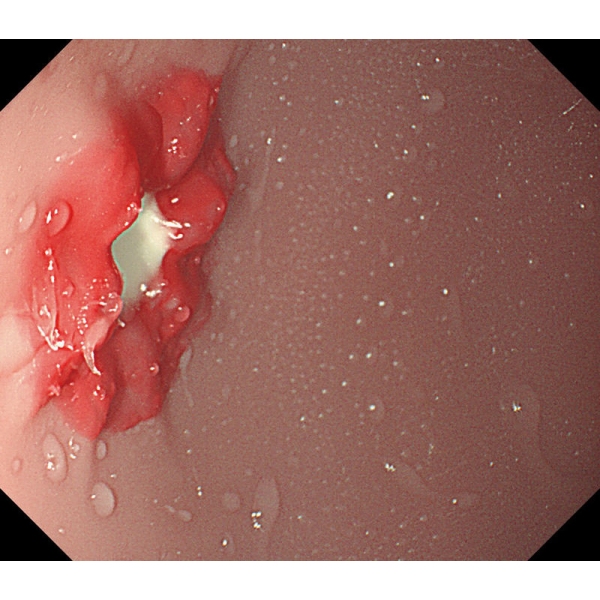

- V želodcu je mogoče opazovati želodčno razjedo in zgodnji rak želodca. Za opazovanje je mogoče pritrditi tudi štiri vrste polipov po Yamadovi klasifikaciji tipov od I do IV.

- V dvanajstniku je mogoče reproducirati razjedo.